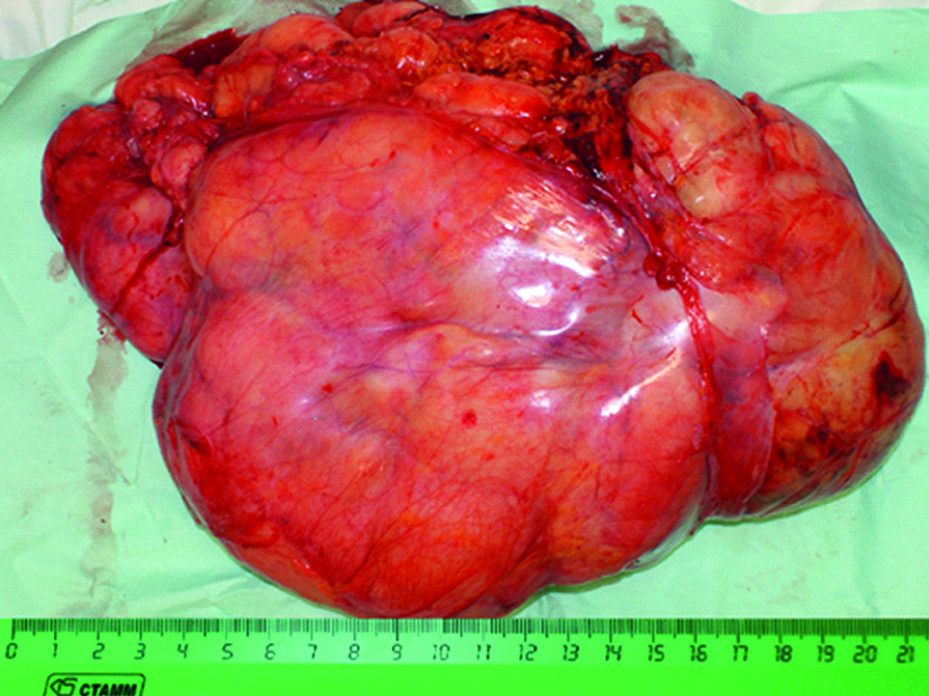

Planned histopathology report: dedifferentiated liposarcoma, G3 (FNCLCC), resection margins are clean, R0 (Fig. 5).

Figure 5. Macropreparation.

Рисунок 5. Макропрепарат.